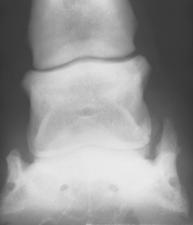

Kaip nurodyta 27 paveiksle, kanopos sąnario OCD pasireiškė 12 % dažnumu. Buvo tirtos rentgenogramos tiek priekinių, tiek užpakalininių galūnių kanopų.

Priekinių galūnių kanopose OCD nustatytas 5 gyvuliams, tuo tarpu užpakalinėse – vienam. 23 pav. paveiksle pavaizduotas OCD pasireiškimo dažnumas, lyginant užpakalinių bei priekinių galūnių kairę ir dešinę puses.

23 pav. OCD pasireiškimo dažnumas, lyginant skirtingų galūnių kanopas.

24 pav. Kanopos sąnario rentgenograma.